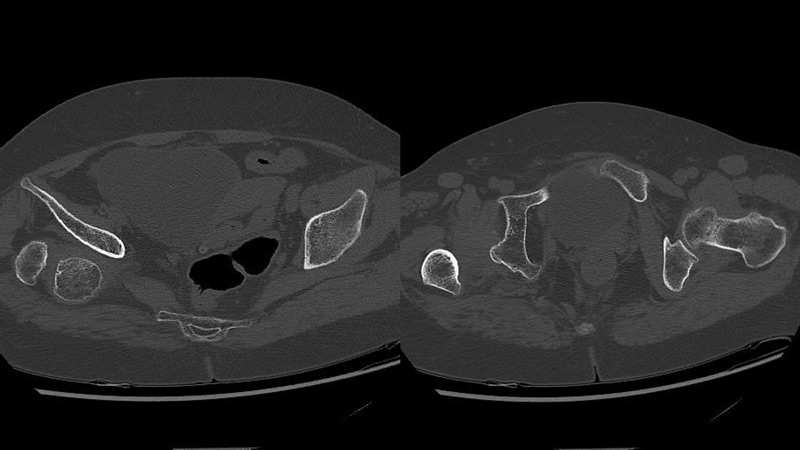

Post-operative X-rays

Management of a hip dysplasia in a middle-aged woman: Post-operative X-rays